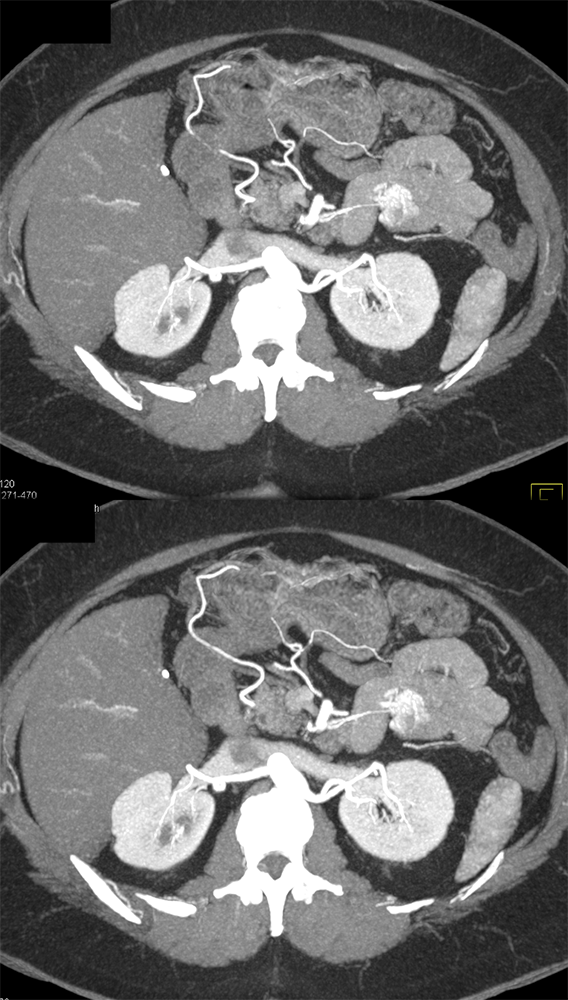

RCC Metastatic to Small Bowel ![]() |

![]() |